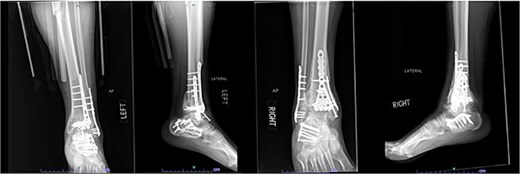

One year after the initial surgery, the left leg healed without any complications. However, the right leg developed nonunion through the distal tibia, along with posttraumatic arthritis. As a result, the patient underwent a right ankle fusion. Additionally, 2.5 years after the index surgery (1.5 years after the ankle fusion), the patient required removal of the right lateral fibular plate due to painful hardware. Six months later (3 years post-index surgery), the patient then underwent subtalar fusion due to post-traumatic arthropathy and ongoing pain (Fig. 2).

Radiographs of patient 1 obtained 3 years after the index procedure, including AP view of the left ankle and lateral and oblique views of the right ankle following subtalar fusion.